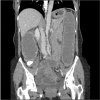

Thoracic endometriosis syndrome is the presence of endometrial tissue in or around the lung. Thoracic endometriosis syndrome consists of four distinct clinical entities: catamenial pneumothorax, catamenial hemothorax, hemoptysis, and pulmonary nodules. Thoracic endometriosis syndrome is a rare and complex condition, and diagnosis is often delayed or missed by clinicians, which can result in recurrent hospitalizations and other complications. Current treatments include hormone therapy and, where warranted, surgical intervention. We report the case of a 48-year-old woman with endometriosis causing bowel obstruction and concurrent catamenial pneumothorax.